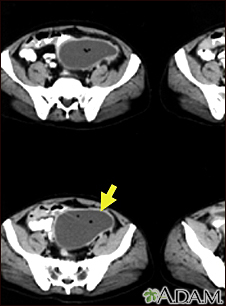

Intra-abdominal abscess - CT scanBackIntra-abdominal abscess - CT scanCT scan of the pelvis showing a large intra-abdominal mass. E-mail FormEmail ResultsName:Email address:Recipients Name:Recipients address:Message: